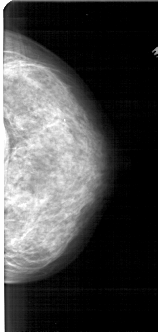

A_1755_1.LEFT_MLO

LEFT_MLO LINES 5491 PIXELS_PER_LINE 2671 BITS_PER_PIXEL 12 RESOLUTION 43.5 OVERLAY